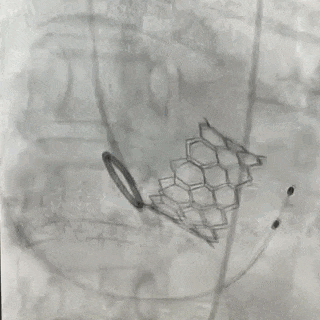

手术经心尖入路,术中植入25# RENATUS®球扩式经导管主动脉瓣。输送器顺利通过,瓣膜精准释放。瓣膜释放位置理想、形态及功能良好,术后无明显瓣中及瓣周反流等并发症。

术中造影

释放后造影